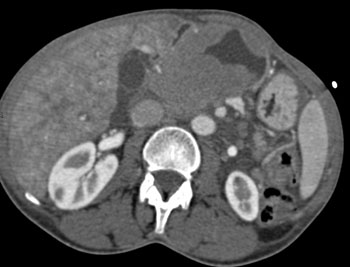

![]() | Question 14: HIV patient with increasing chest discomfort. The study was requested to rule out a pulmonary embolism. What is the diagnosis? |